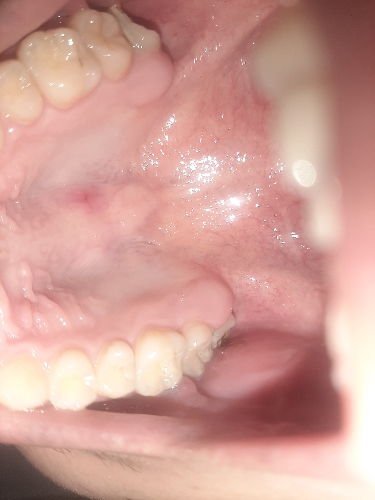

Em bị đau và có nổi cục nhỏ trên khẩu cứng hàm. Bác sĩ cho em hỏi bị gì và em nên làm gì ạ?